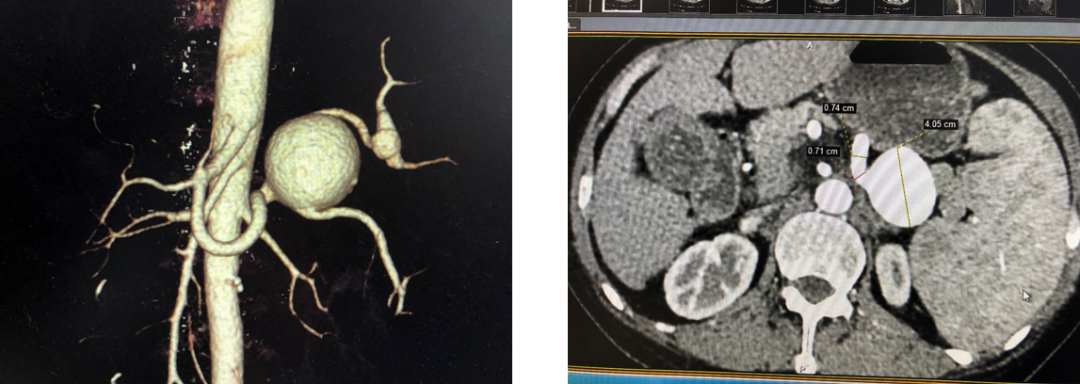

病例6 脾动脉瘤Viabahn支架隔绝

图为:术后复查